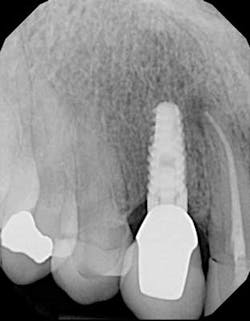

One year post-insertion radiographs indicate that bone levels around the implant remain stable. Clinical results 1.5 years post-insertion reveal gingival levels to be stable and healthy, and the patient is very pleased with the esthetic result of his treatment.